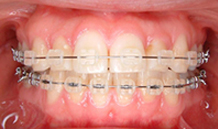

2か月後です。反対咬合は治っています。現在は正常な噛み合せになりました。

これからまだ永久歯に生え替わるので、注意深く定期的に観察していきます。生え替わった後に、また反対咬合になりこともあります。